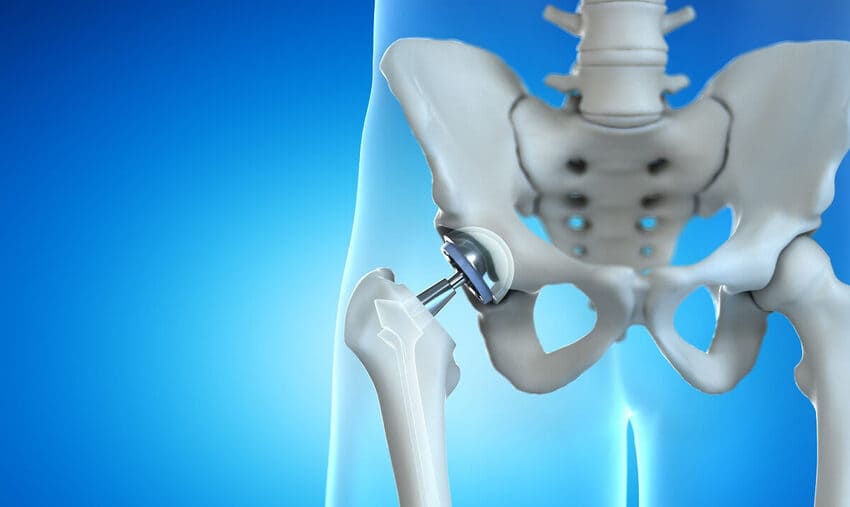

Vad är en total höftledsoperation?

Total höftledsoperation i Turkiet i Istanbul är ett kirurgiskt ingrepp där sjukt brosk och ben i höftleden ersätts kirurgiskt med konstgjorda material.

Vilka andra typer av höftproteser finns det?

- Partiell höftledsprotes

Höften är en kulled. Den kan skadas av sjukdom eller slitage. Om endast en del av leden är skadad kan en partiell höftprotes övervägas.

Vid en partiell höftledsoperation lämnas höftleden i allmänhet intakt. Lårbenets huvud ersätts med en konstgjord komponent som liknar den som används vid en total höftledsoperation. Ibland placeras en anordning på benet så att toppen av lårbenet inte behöver skäras av. - Minimalt invasiv höftledsoperation